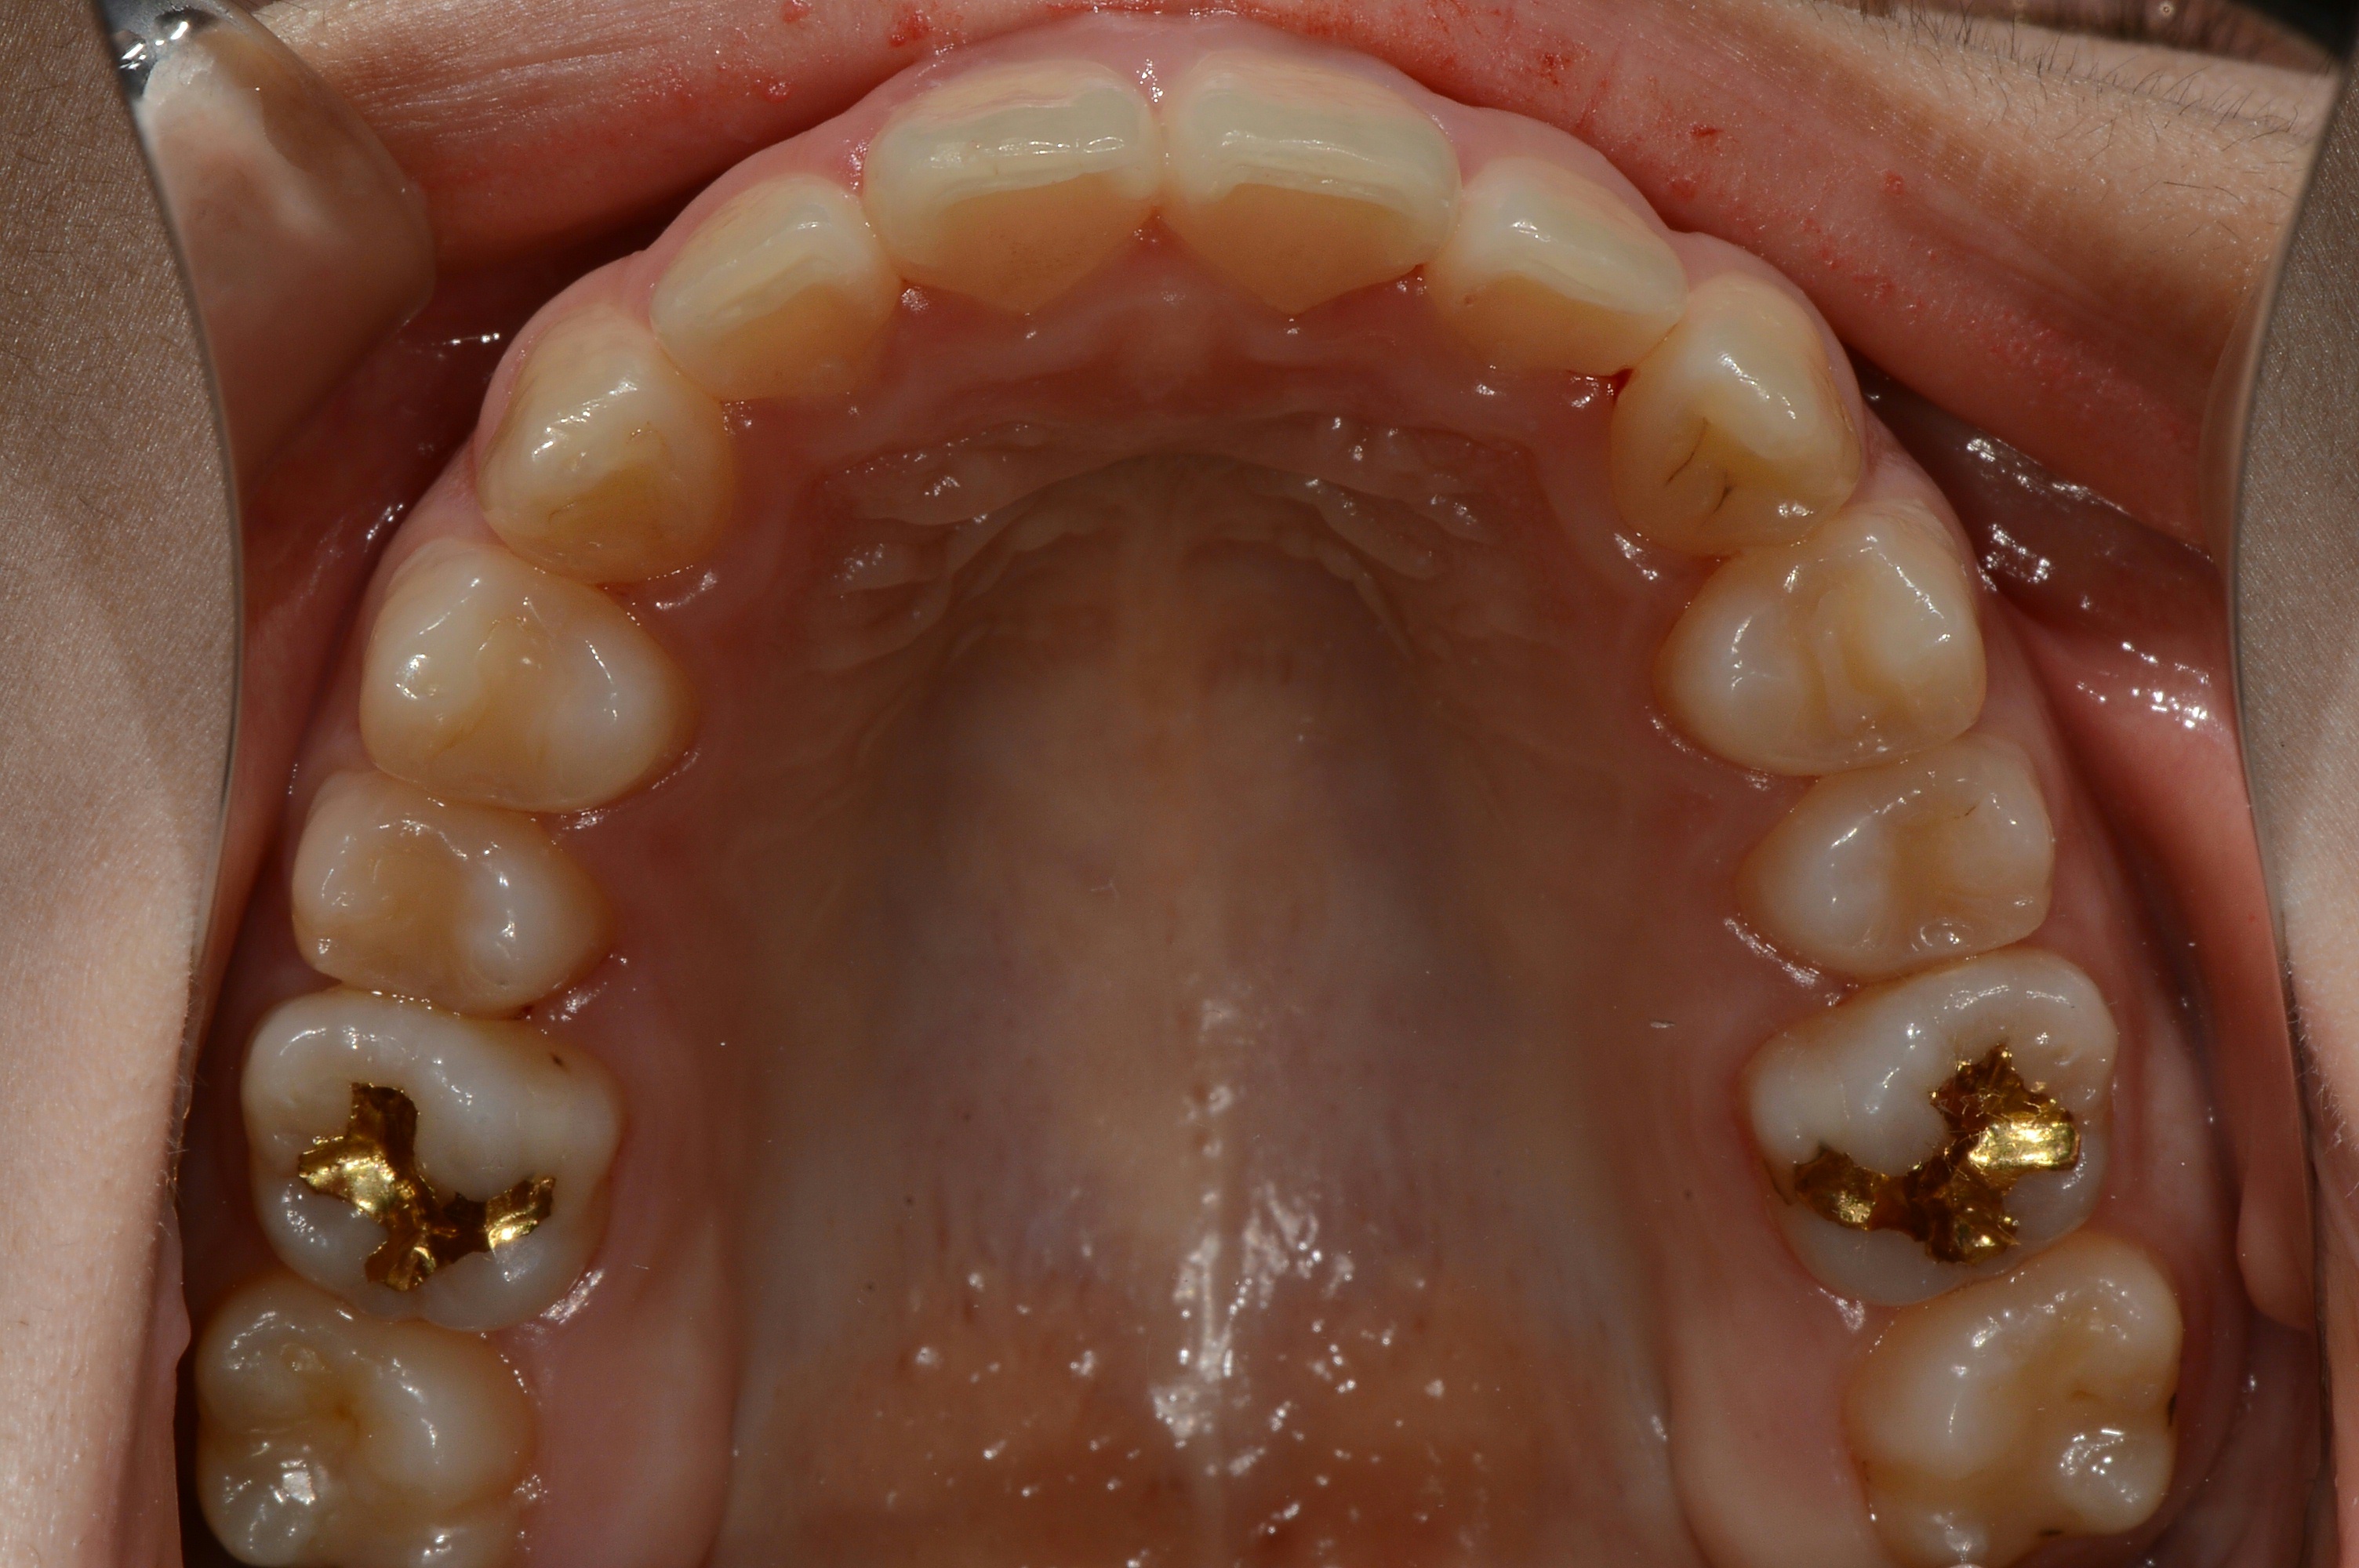

치료 전 사진입니다.

치료 후 사진입니다.